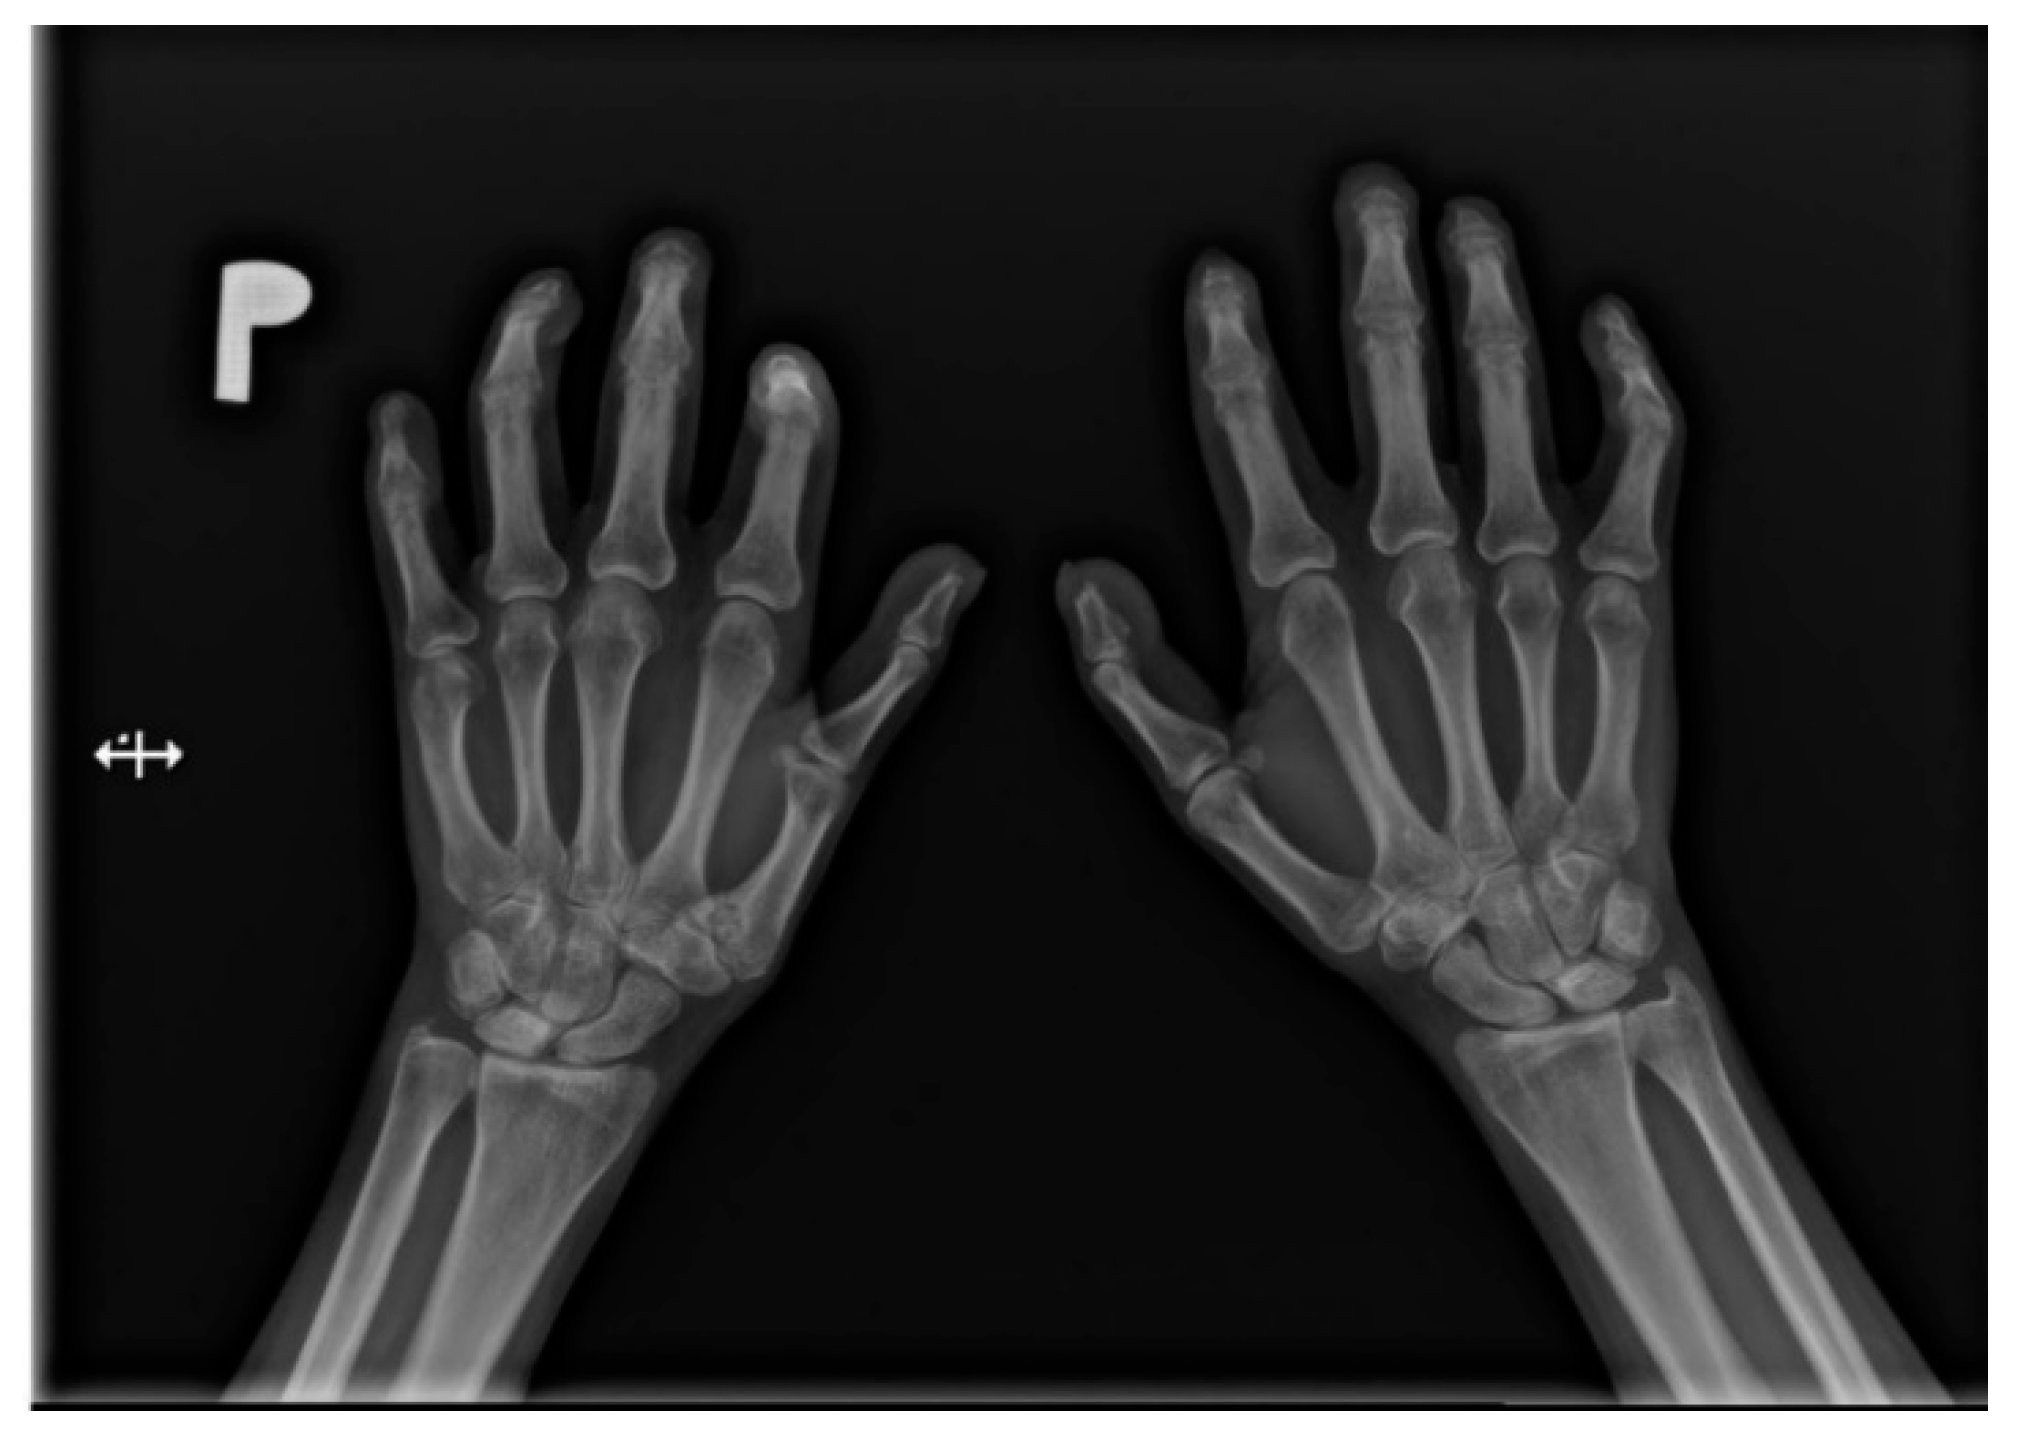

Figure 2.

A-P view of the hand radiograph in a patient with systemic sclerosis shows acro-osteolysis of the distal phalanx of the first, second, third, and fourth fingers of both hands. Additionally, small joint contractures and areas of calcinosis in the fingertips are visible.

Soft-tissue calcifications are observed in about 46% of patients [20]. Both subcutaneous and periarticular locations are possible. Periarticular calcifications were reported not only in typical peripheral regions (e.g., in the hand), but also in less frequent areas, such as the paraspinal site, including even the spinal canal itself, with a possibility of its narrowing [15].

Flexion contractures are present in approximately one-third of patients. Their most common sites are the metacarpophalangeal joints and interphalangeal joints. They are more common in diffuse scleroderma [25].